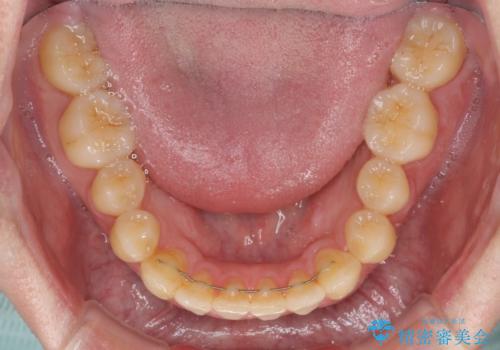

前歯のクロスバイト インビザラインによる矯正治療

- 上下のクロスバイトと前歯のデコボコを気にして来院された患者様です。

インビザラインを用い、IPR(歯と歯の間を削る)と歯列全体を拡大させることで、歯並びを整えていくこととしました。

- 矯正治療後の保定が不十分だと後戻り(元の位置に戻ろうとする動き)をします